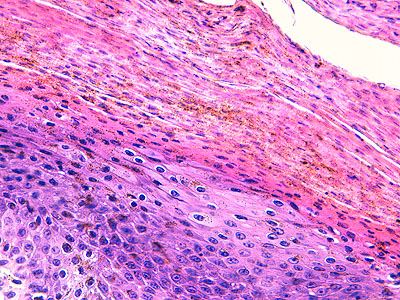

Photo 3 (Hémalun Eosine X 100) : aspect bleu-blanc-rouge à plus fort grossissement,

bleu pour hyperplasie des couches basales, blanc pour vacuolisation des acanthocytes

sous-cornés et rouge pour parakératose de la couche cornée. Le derme superficial est

le siège d’un infiltrat inflammatoire mononucléé périvasculaire modéré.

Légendes de la Photo 3 :

- Flèche bleue pour hyperplasie des couches basales

- Flèche blanche pour vacuolisation des acanthocytes sous-cornés

- Flèche rouge pour parakératose de la couche cornée

- Étoile rouge : Le derme est faiblement à modérément inflammatoire